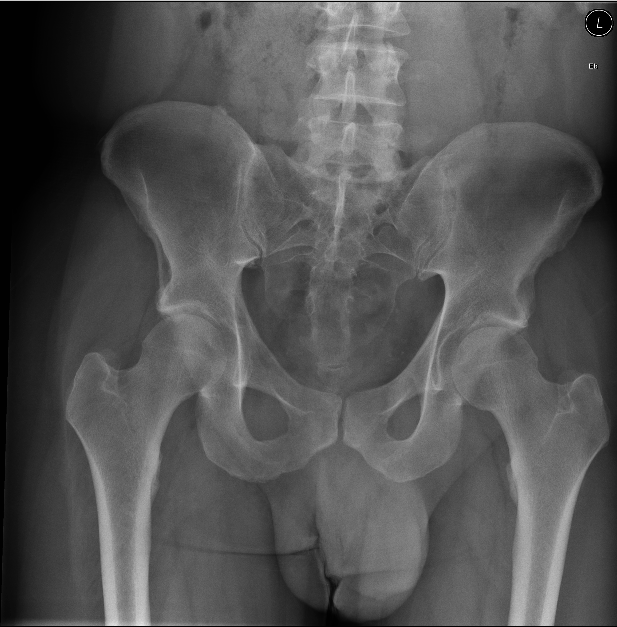

| 20 |

Abnormal rt nof |

Normal |

Incorrect |